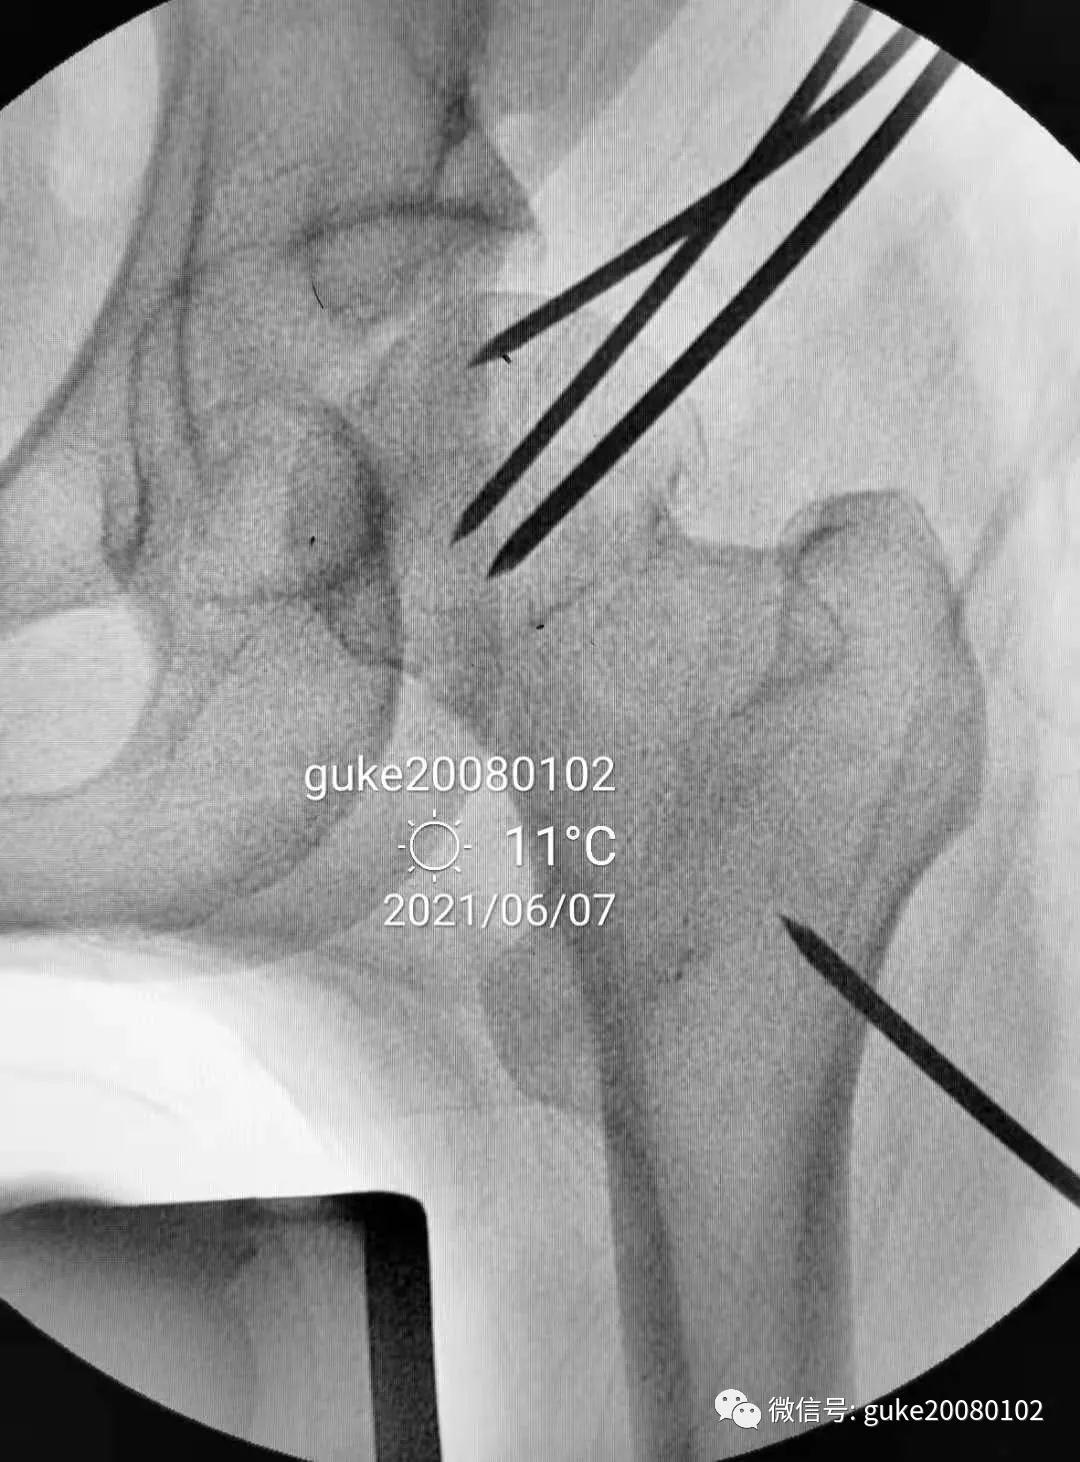

患者置于牵引床上,固定骨盆,尝试Ledbetter法复位,透视见复位不佳。骨折断端崁插,股骨头外翻。

- 在大转子顶点近端5厘米处,经皮向股骨头上方插入直径2.0mm克氏针两枚,敲击克氏针至骨质,撬拨头颈骨折块复位。

- 撬拨力量偏小,骨折复位不足。再插入一枚2.5mm克氏针,接力撬拨,骨折复位。

1.正侧位观察骨折复位,骨小梁走形恢复。崁插骨折复位。

2.外侧植入克氏针一枚,临时固定骨折。